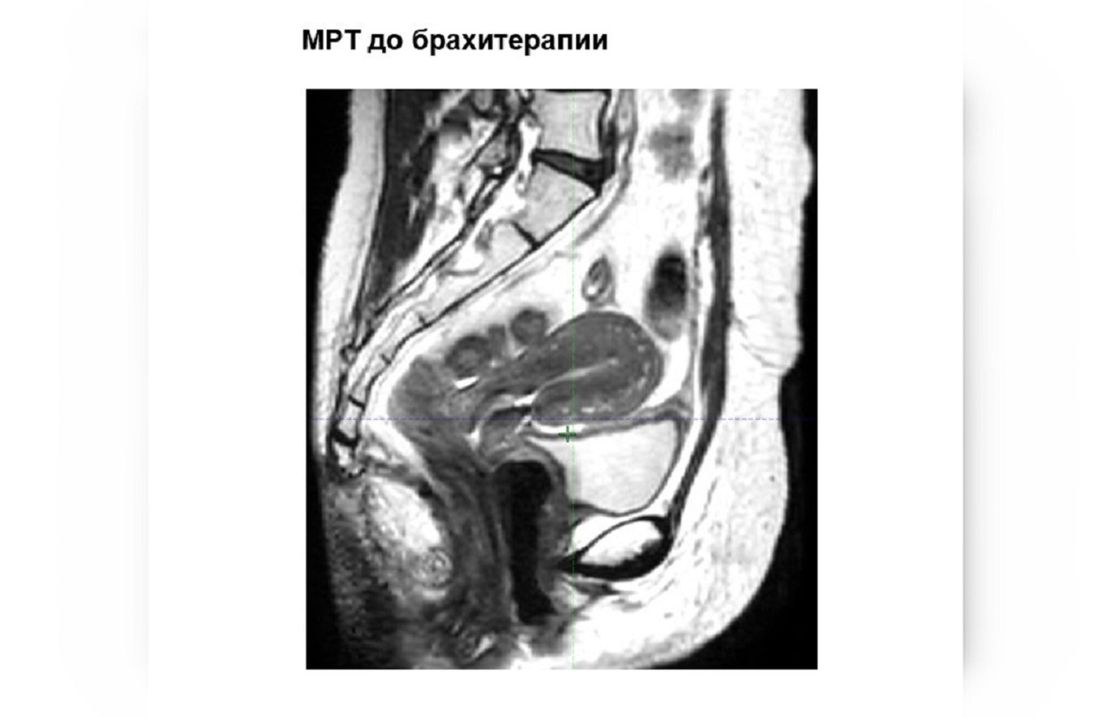

Терапия проходила в 2 этапа. Сначала пациентке провели химиолучевую терапию наружного облучения. Затем – брахитерапию, при которой источник излучения подводится непосредственно к опухоли.

"После первого этапа мы оцениваем результат на МРТ, определяем остаточный объем опухоли и планируем брахитерапию", — объясняет радиационный онколог ННОЦ Гайни Олжатаева.

В центре применяется МРТ-симулятор 1,5 Тесла, который позволяет значительно повысить точность визуализации опухоли и считается важным стандартом при планировании 3D-брахитерапии. В отличие от компьютерной томографии, она позволяет четче увидеть границы опухоли и точнее рассчитать зону облучения. Дополнительно используется система фиксации пациента, которая помогает сохранять одинаковое положение на всех этапах и обеспечивает точную доставку дозы.

Фото: ННОЦ